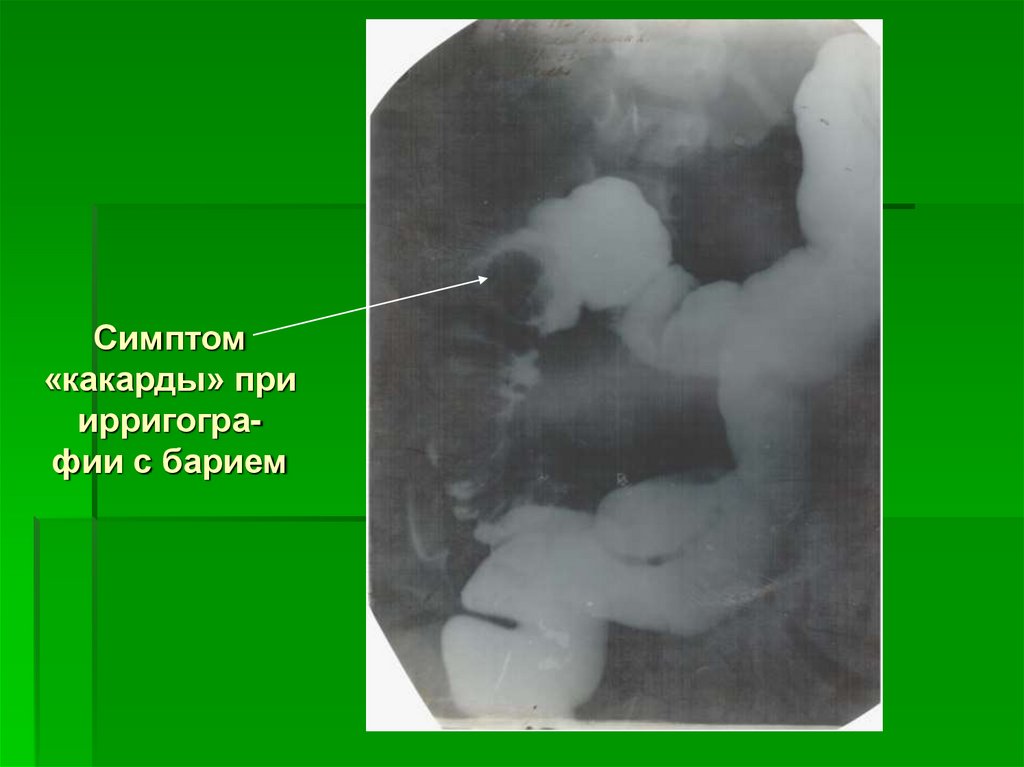

Симптом

«какарды» при

ирригографии с барием